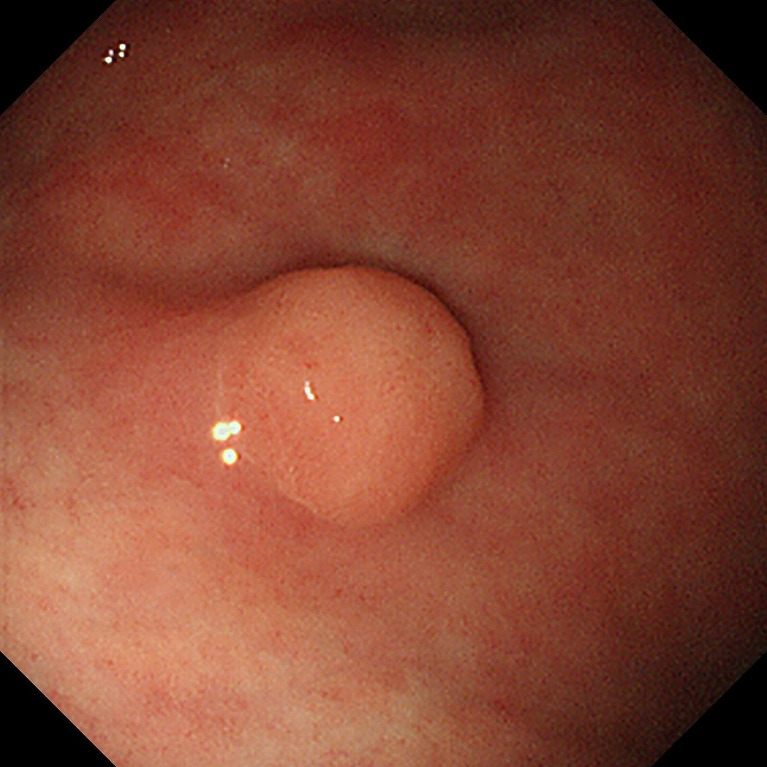

위암, 조기위암 선별

조기 위암은 내시경적 절제술만으로도 완치가 가능한 경우가 많기 때문에 최대한 이른 시기에 발견하는 것이 중요합니다.

육안 소견만으로는 정상 점막과 거의 구별이 안 되는 경우가 많아,

- 색조의 미세한 차이

- 얕은 함몰

- 표면 패턴 변화

등을 근거로 조직검사를 시행합니다. 이 단계에서의 조직검사는 생명 예후와 직결되는 진단 과정입니다.